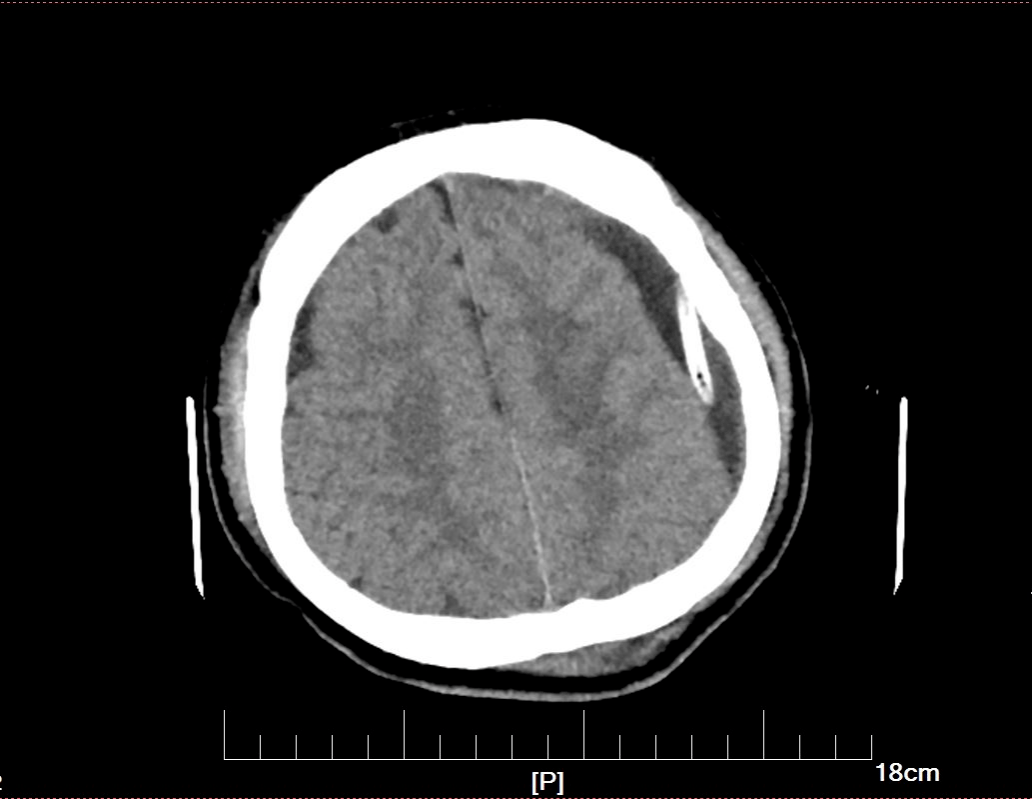

左侧硬膜下血肿:呈等密度,有占位效应,中线结构移位.